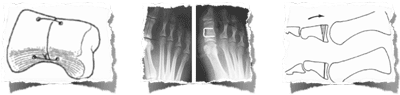

1 - L'émondage articulaire : 1er temps commun à toutes les techniques (résection des ostéophytes et des corps étrangers intra-articulaires)

2 - Cheilectomie décrite en 1965 : émondage + arthroplastie modelante emportant le 1/3 dorsal de la tête ; elle soulage la douleur en 3 à 6-12 mois ; elle n'évite pas l'aggravation de l'arthrose mais en général les ostéophytes ne récidivent pas. Le gain de mobilité est la moitié de celui obtenu en peropératoire si le patient est volontaire et porte une attelle nocturne ; le résultat est habituellement stable à 4 mois. Elle ne coupe pas les ponts vers une autre chirurgie. L' appui est immédiat à plat avec kinésithérapie.

3 - Les techniques de décompression articulaire peuvent se faire en métatarsien ou phalangien :

a- les ostéotomies de la première phalange

- de flexion dorsale (Moberg : facilite la phase finale du pas)

1 - L'ARTHRODESE :

Elle constitue l'intervention de référénce.

Elle supprime immédiatement la douleur (et la mobilité !) mais le réglage de la position est important en maintenant un espace avec le 2° orteil et une rotation neutre.

Le but de l'intervention est de réséquer les ostéophytes, gênant le chaussage et bloquer la première articulation métatarso-phalangienne par avivement des surfaces articulaires et ostéosynthèse par agrafes, vis ou broches.

Des chaussures post-opératoires sont nécessaires 45 jours pour limiter le risque de pseudarthrodèse (défaut de consolidation).